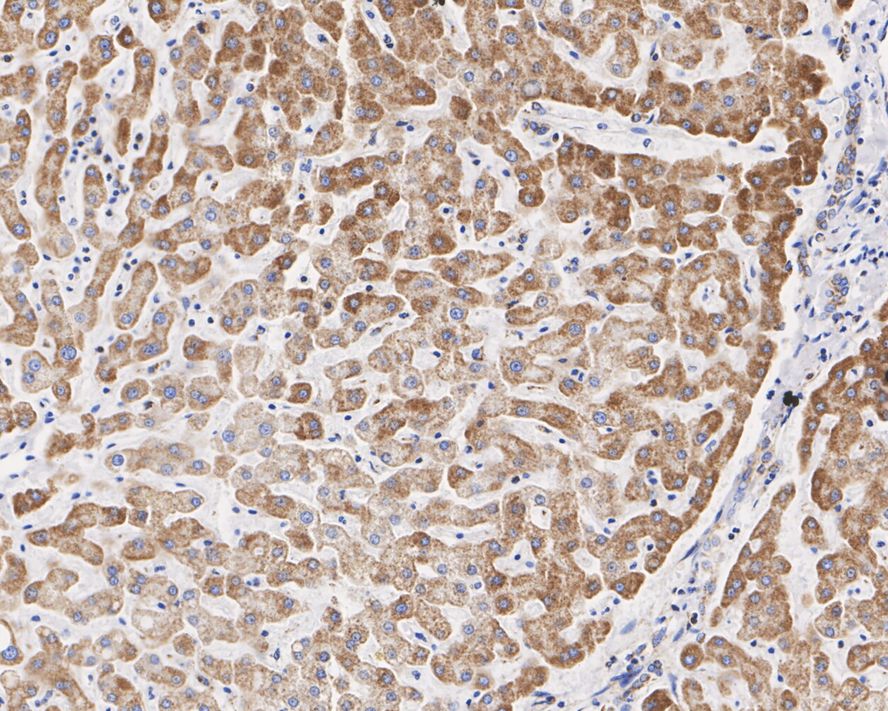

Catalog# HA721872

UQCRC2 Recombinant Rabbit Monoclonal Antibody [JE32-56]

IHC-P